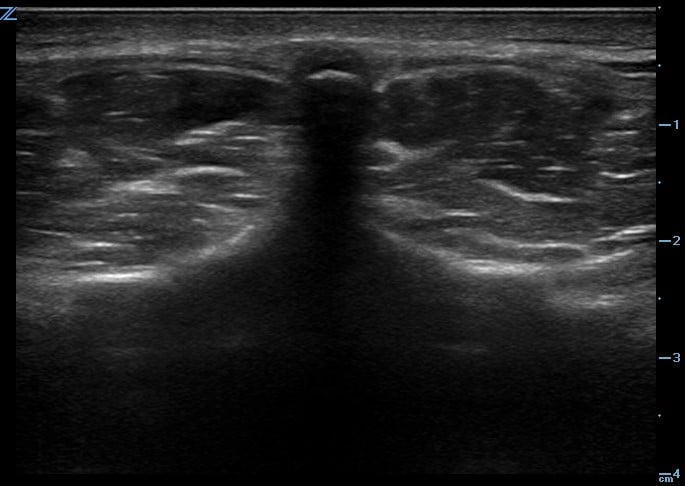

One recommended approach is to start with the probe in transverse position at the level of the sacrum and scan superiorly, sequentially identifying the spinous processes of L5, L4, L3, and L2. In the transverse orientation, spinous processes are seen as small, hyperechoic marks with dense vertical shadowing (Figure 1). With the probe centered over a spinous process, the operator uses a clean towel to wipe off excess gel, and a skin marker to place a vertical hash mark above and below the midline of the probe (Figure 2). Next, the probe is placed in longitudinal orientation over the same spinous processes, with the indicator toward the patient’s head. In this view, spinous processes will appear as wider, hyperechoic areas with distal shadowing (Figure 3). When two or more spinous processes are simultaneously visualized, the space between them is the area available for needle insertion. The skin is marked again, this time with horizontal hash marks extending outward from the midline of the probe (Figure 4).

Figure 1. Ultrasound image of spinous process in transverse plane.